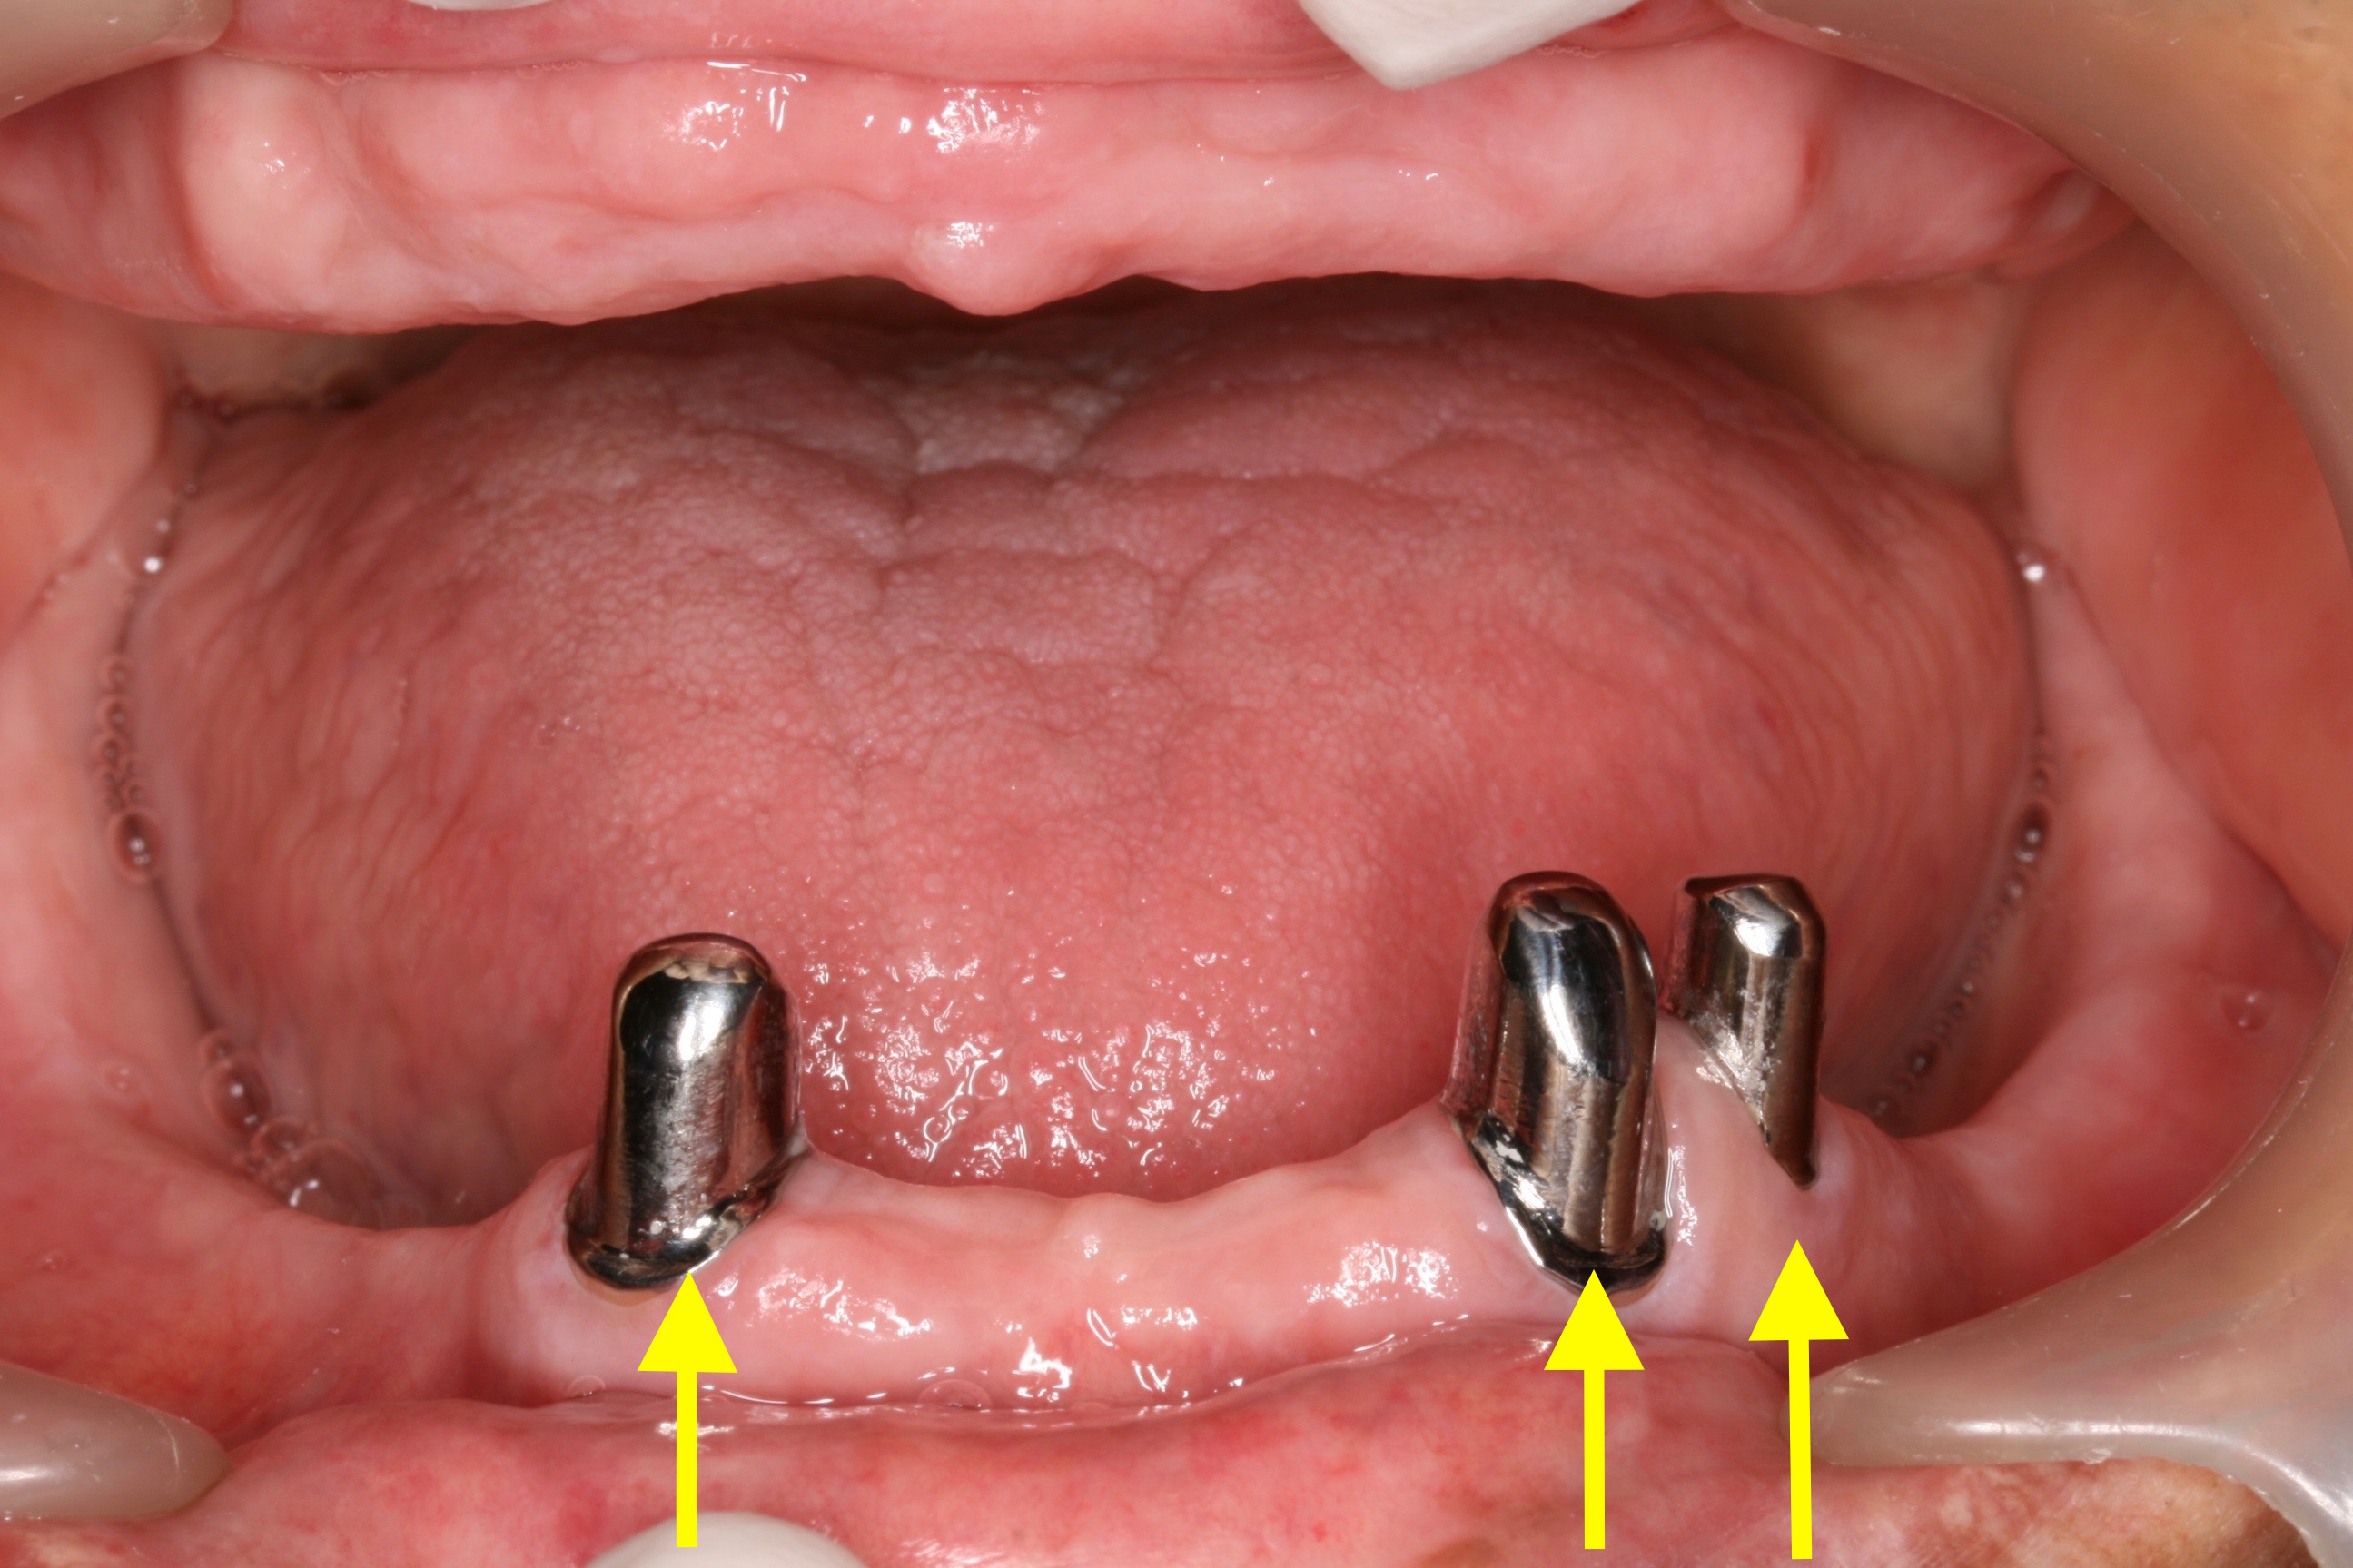

ケース NO.2 ⬆︎ 残した歯 ⬆︎ 抜いた歯

上がレジリエンツテレスコープ義歯、下が総入れ歯

この患者様は下アゴが分からない程痩せてしまっているため、

高度な技術が必要となります。